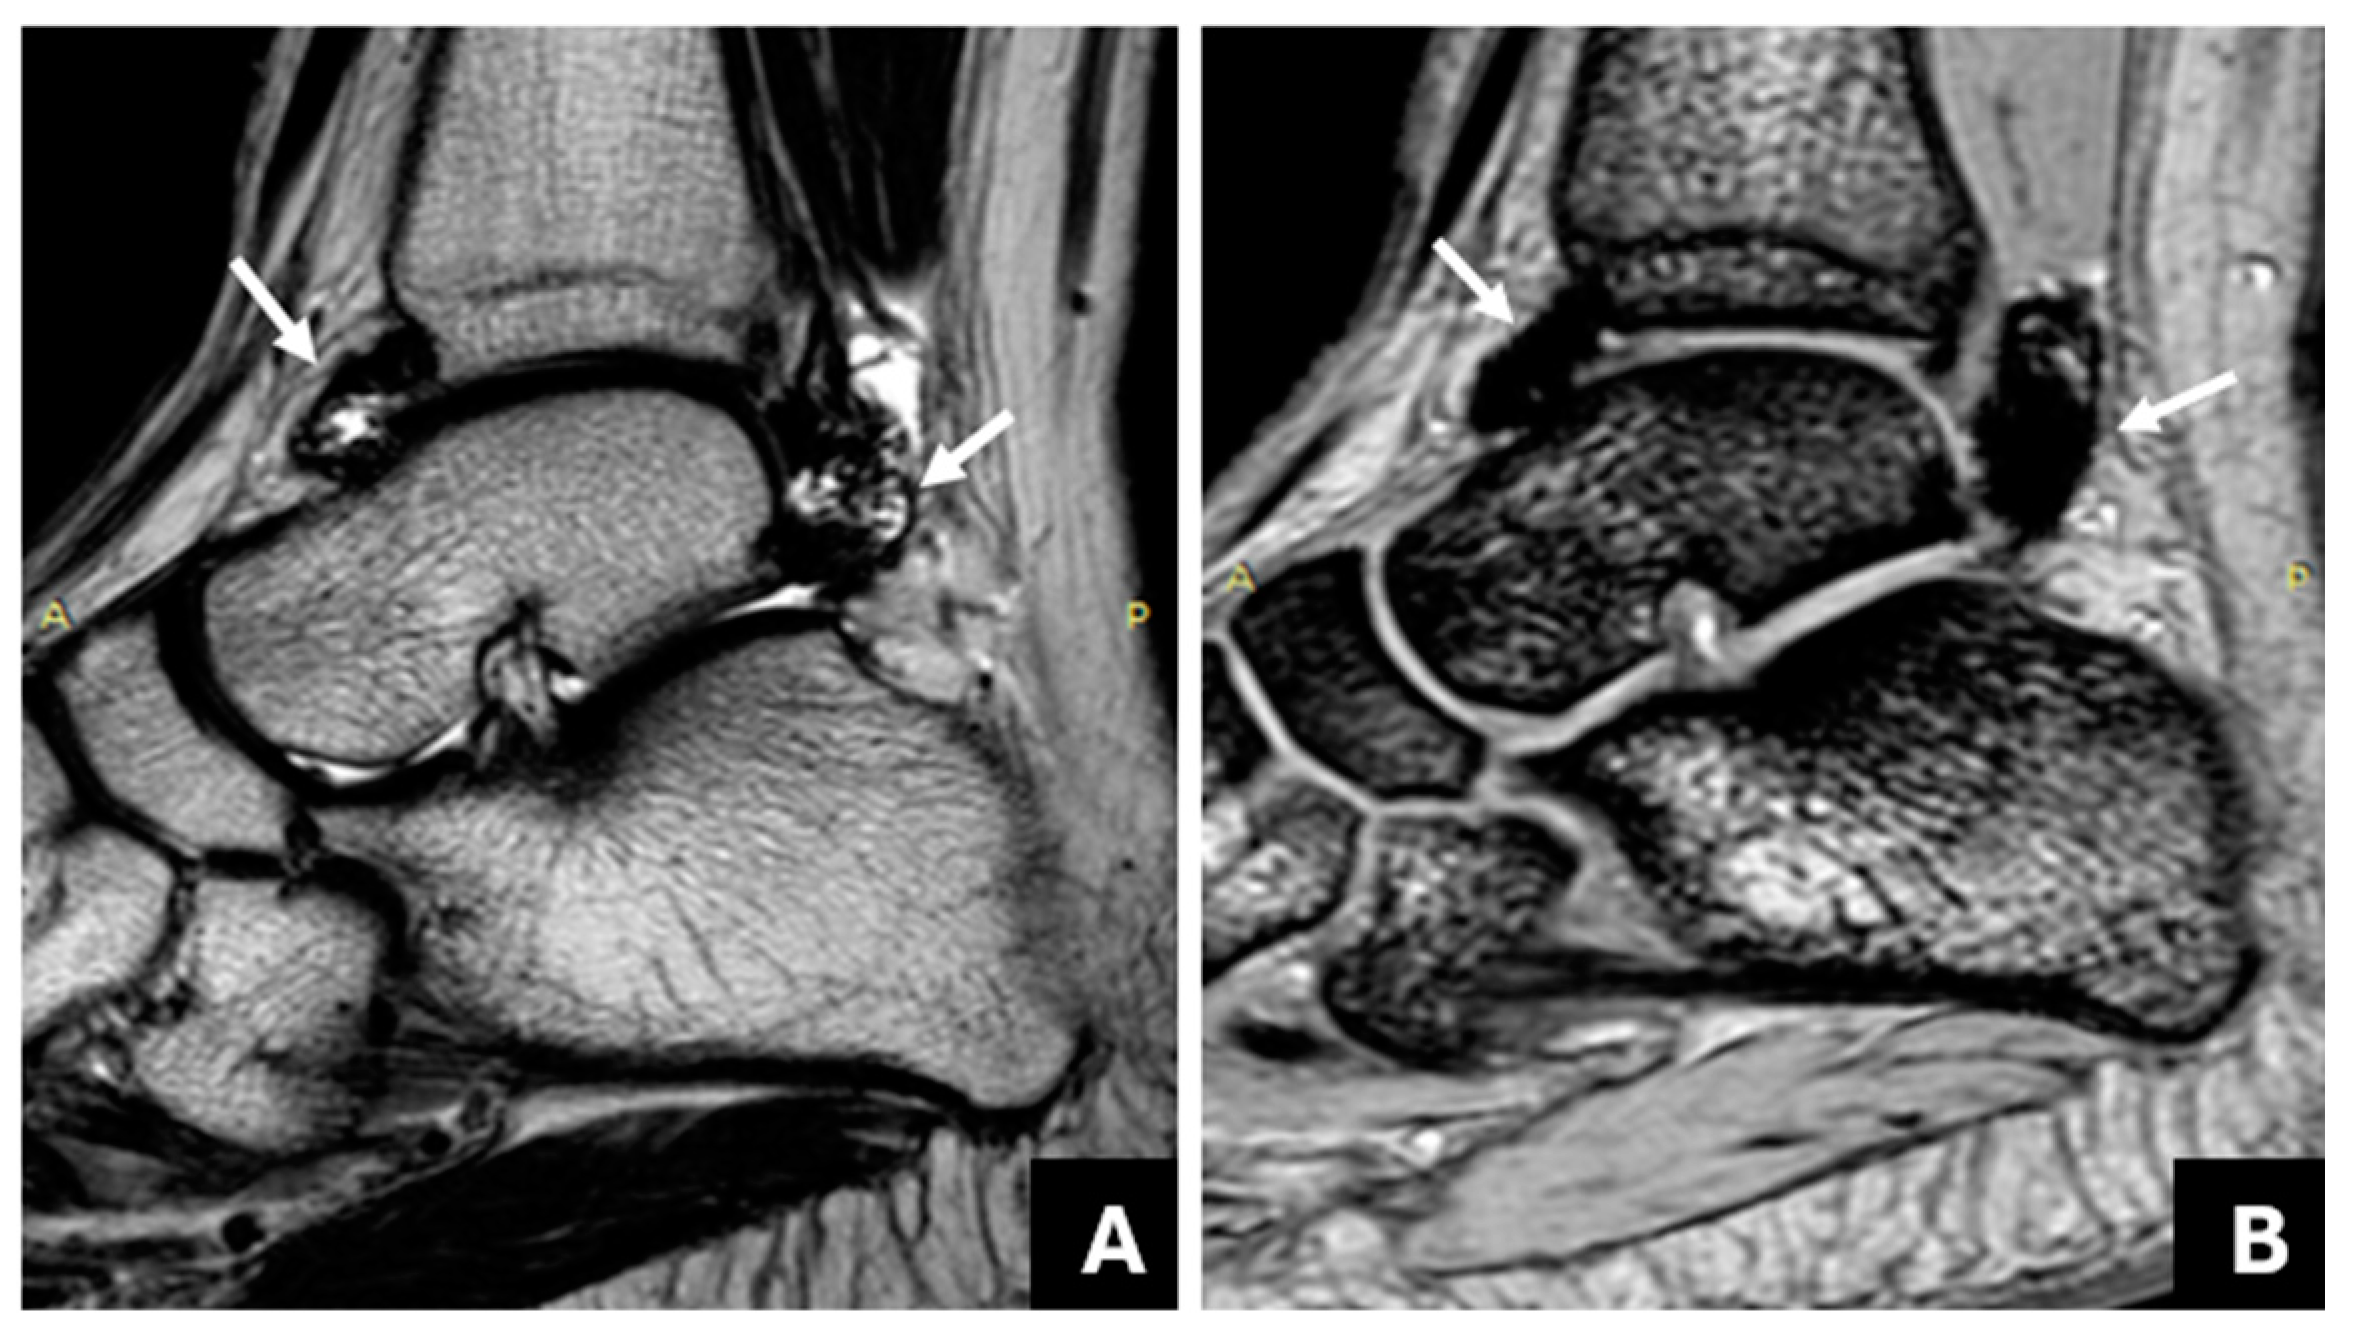

3.1. Detection of Joint Hemosiderin Deposition with mGRE Sequence: Inter-Reader Agreement

3.2. The Association of Joint Hemosiderin Deposition with Synovial Thickening, Effusion, and Osteochondral Changes (OCC)

3.3. Association of Joint Hemosiderin Deposition with the Number and Chronicity of Joint Bleeds and Clinical Score